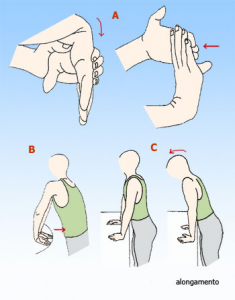

Síndrome do Túnel Carpico

Esta doença ocorre quando o Nervo Mediano que passa no Canal Carpico fica comprimido provocando sintomas de dormência e formigueiro principalmente nos dedos, indicador anelar e médio podendo com o tempo derivar em situações de dor muito intensa. Esta situação é induzida por fenómenos de stress continuado na região em causa.

Para prevenir esta doença deve procurar com alguma frequência fazer alongamento dos músculos flexores dos dedos e dos punhos.